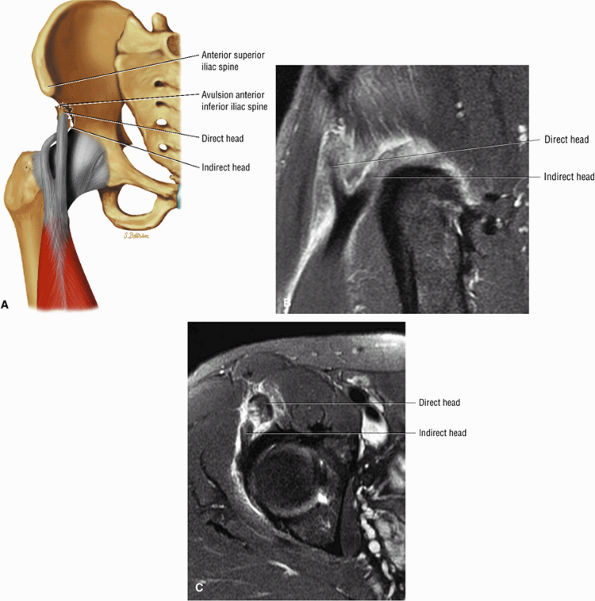

FIGURE 3.6 ● RECTUS FEMORIS The rectus femoris flexes the thigh (hip) and extends the leg (knee). Of the four quadriceps muscles (the vastus lateralis, vastus medialis, vastus intermedius, and rectus femoris), only the rectus femoris has an origin that crosses the hip joint. Soccer, football, and basketball players and track and field athletes are at risk for distal musculotendinous junction injuries and proximal intrasubstance tears of the musculotendinous junction of the indirect head of the rectus.

![]() |